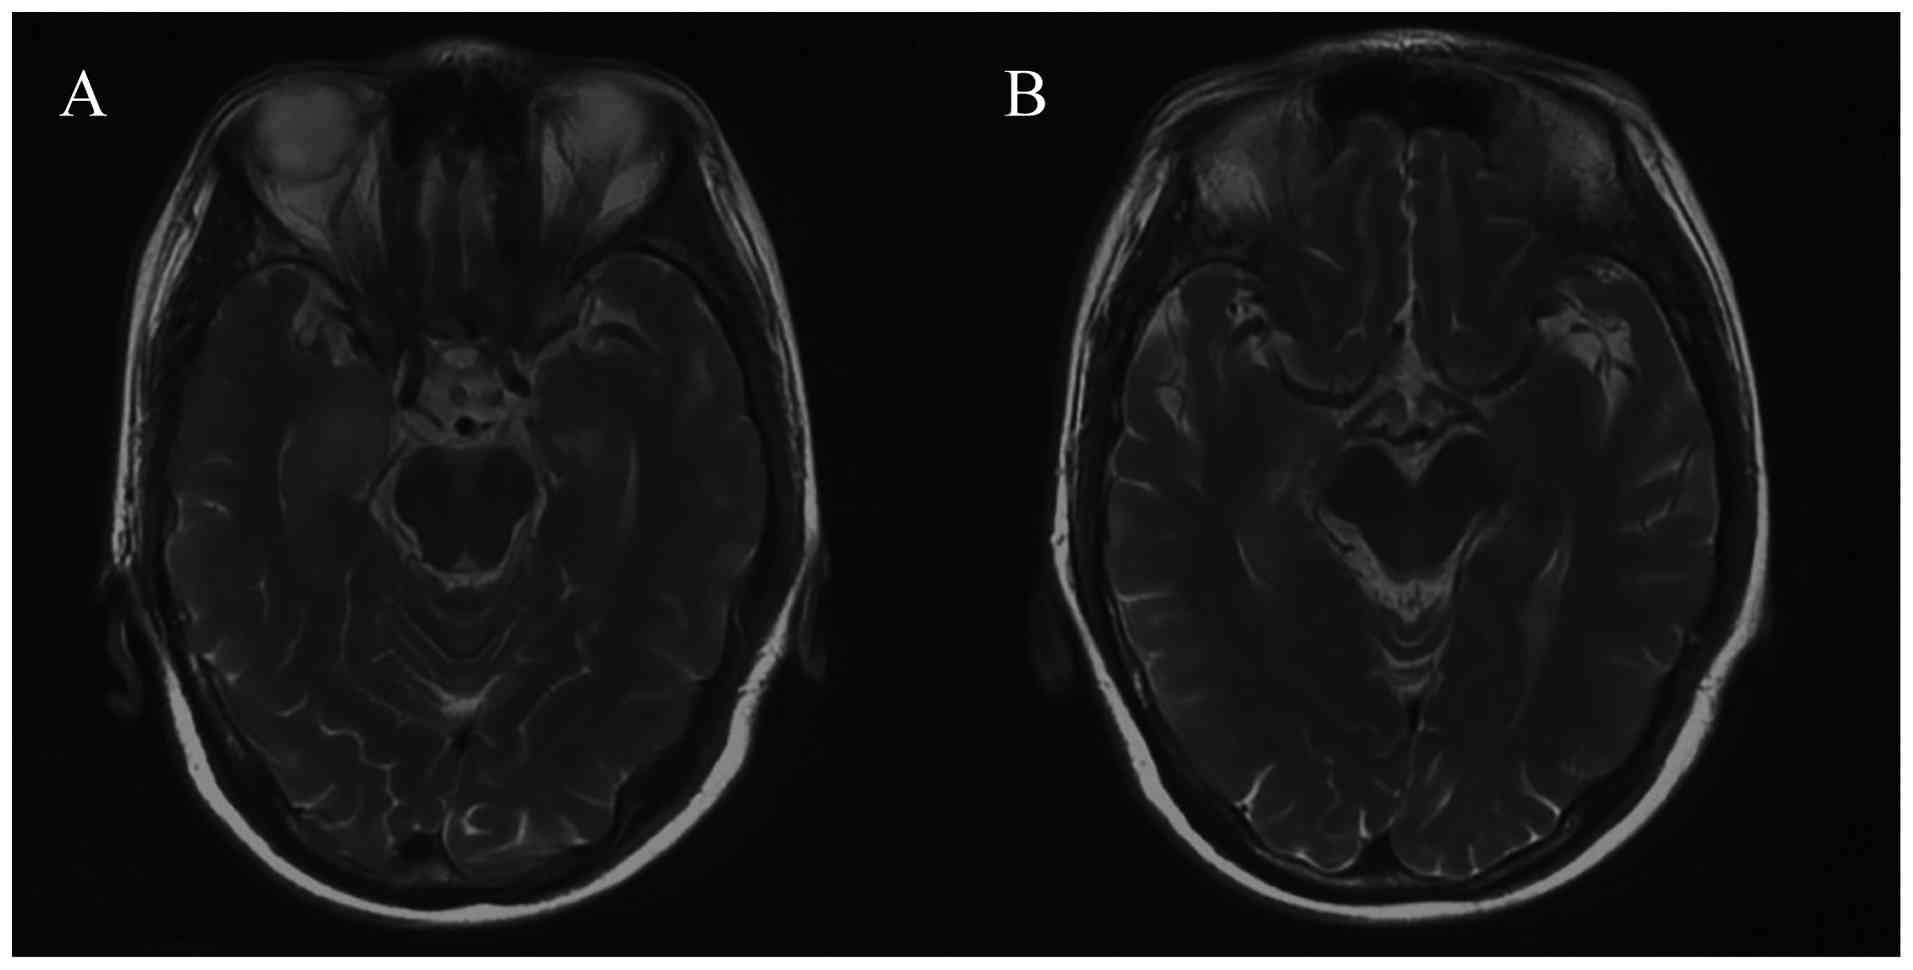

A diagnosis of Hu-associated limbic encephalitis induced by ICI was considered, and immunotherapy was therefore withheld. High-dose steroids (methylprednisolone 1 g per day for 2 days, then 2 mg/kg per day for 5 days, then 1 mg/kg per day for 7 days, then tapered by 0.125 mg/kg per day every two weeks until discontinuation) and intravenous immunoglobulin (400 mg/kg per day for 5 days) were introduced. Subsequently, 1 month later, the patient's neurological symptoms remained stable. In September 2020, the white blood cell count in CSF was normal (2/µl), anti-Hu antibodies continued to be detectable in the CSF, and MRI of the brain indicated no significant change compared with the previous MRI (Fig. 5). The patient died of tumor progression in March 2021. During this period, her neurological symptoms remained stable, and no additional magnetic resonance imaging or cerebrospinal fluid examinations were performed.

Brain magnetic resonance imaging (A)

before and (B) after 1 month of treatment depicted no significant

change in the lesions compared with the previous scan, with respect

to T2 signal.

Figure 5.

Brain magnetic resonance imaging (A) before and (B) after 1 month of treatment depicted no significant change in the lesions compared with the previous scan, with respect to T2 signal.